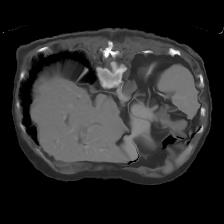

In clinical practice, well-aligned multi-modal images, such as Magnetic Resonance (MR) and Computed Tomography (CT), together can provide complementary information for image-guided therapies. Multi-modal image registration is essential for the accurate alignment of these multi-modal images. However, it remains a very challenging task due to complicated and unknown spatial correspondence between different modalities. In this paper, we propose a novel translation-based unsupervised deformable image registration approach to convert the multi-modal registration problem to a mono-modal one. Specifically, our approach incorporates a discriminator-free translation network to facilitate the training of the registration network and a patchwise contrastive loss to encourage the translation network to preserve object shapes. Furthermore, we propose to replace an adversarial loss, that is widely used in previous multi-modal image registration methods, with a pixel loss in order to integrate the output of translation into the target modality. This leads to an unsupervised method requiring no ground-truth deformation or pairs of aligned images for training. We evaluate four variants of our approach on the public Learn2Reg 2021 datasets \cite{hering2021learn2reg}. The experimental results demonstrate that the proposed architecture achieves state-of-the-art performance. Our code is available at https://github.com/heyblackC/DFMIR.

翻译:在临床实践中,如磁共振(MR)和光谱成像(CT)等非常相近的多模式图像可以一起为图像制导疗法提供补充信息。多模式图像登记对于这些多模式图像的准确匹配至关重要。然而,由于不同模式之间复杂的和未知的空间通信,这仍然是一项非常艰巨的任务。在本文中,我们提议采用新的、基于翻译的、不受监督的变形图像登记方法,将多模式登记问题转换成单一模式。具体地说,我们的方法包括一个无歧视翻译网络,以便利对登记网络的培训,以及一种有偏差的对比性损失,以鼓励翻译网络保存对象形状。此外,我们提议取代在以往多模式图像登记方法中广泛使用的一种对抗性损失,目的是将翻译的输出纳入目标模式。这导致一种不统一的方法,不需要地面图解或对齐图像来进行培训。我们评估了公共学习2MReg20的四种变式方法,我们在公共实验2Regmal-ress productions 2021我们提议的实验性结构中实现了2021号的运行结果。